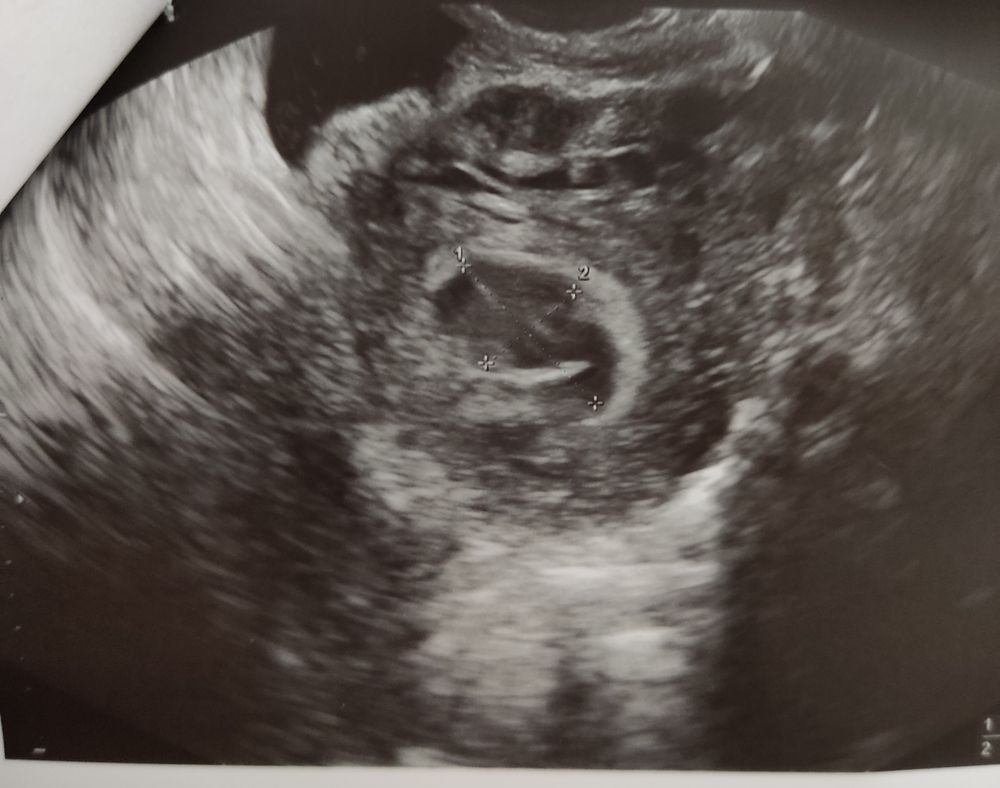

Лекси, нет, не сосуд вовсе.... Я в стационаре на сохранение сейчас, отслойка и тонус

У меня была гематома 3*4 см, кровь лилась рекой - все закончилось хорошо